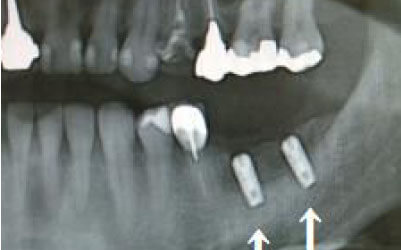

2 神経を傷つけるリスク

顎の骨の中には神経が通っており、インプラント治療の際にそれを傷つけてしまうリスクがあります。

しかし、当院では事前にCT撮影を行い、神経までの距離を三次元的に正確に把握した上で治療計画を立てるため、リスクをしっかり回避できます。

さらに、骨を削りすぎないようにするための専用のストッパーも導入しており、安全性には十分に配慮しています。